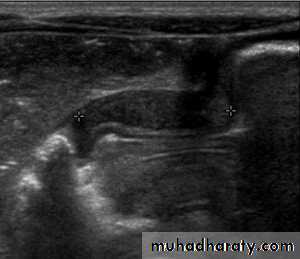

In a normal situation, the pyloric muscle thickness (diameter of a single muscular wall on a transverse image) should normally be less than 3 mm (most accurate 3) and the length (longitudinal measurement) should not exceed 15 mm.